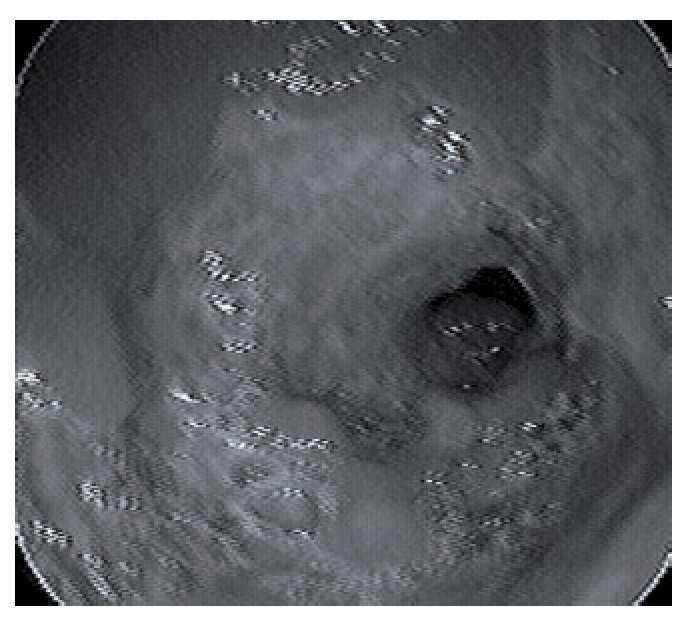

Figura 3. Imagen endoscópica del antro gástrico con mucosa ulcerada, friable, con afectación circunferencial alrededor del orificio pilórico, alternando con áreas de mucosa indemne.